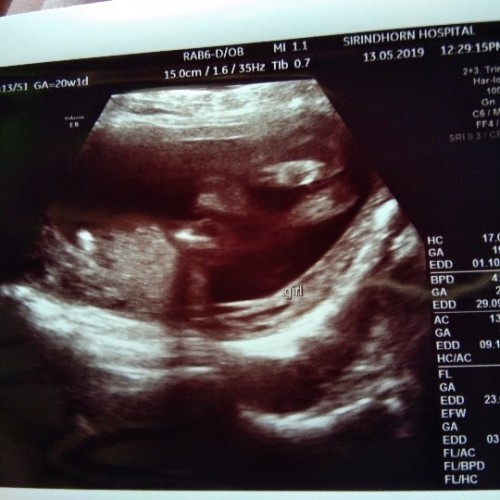

ลูกสาวจ้าาา..

ซาวตอน21w ค่ะ